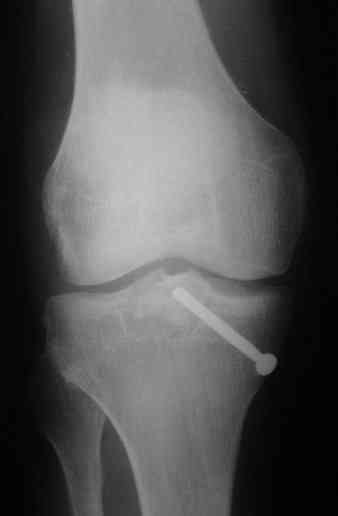

Операция из разряда травматологической "экзотики" прошла успешно. Доступ понравился:анатомичный, хорошая визуализация, удобно работать и оператору и ассистентам. Наложили пневможгут, но воспользовались им только на этапе ревизии сустава. Фрагмент развернулся на 90 град. на 2-ух "жгутах": медиально - сухожилие m.semitendinosus, латерально - задняя крестообразная связка. Мобилизовали,развернули и уложили на место без особого труда. Фиксировали отмоделированной 1/3-трубчатой пластиной. Мениск оказался неповрежден. Сустав стабилен. Обошлись без

иммобилизации, планируем начать ранние движения. Остальное на фото, дополнительно приложены корональные срезы КТ.

> How was the EUA after fixation of this fracture I wonder?

Very slight hint on posterior drawer. Mediolaterally very stable.

> I have trouble imagining this as the only injury inside that knee.

You are not alone. ;-)

At the opposite side he has avulsion (shear?) of the fibular stiloid.

It is of course only butress, an artificial border of the plateau.

> Did you not want to fix it with a short LCP.

No advantage of LCP for the case.